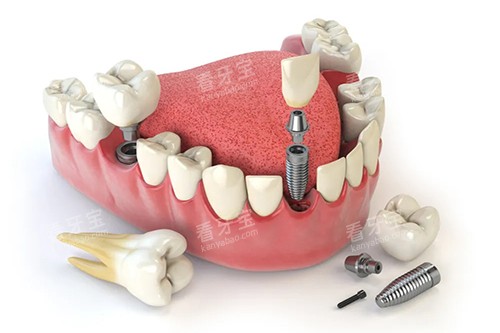

在种植牙方面,医生们熟练掌握各种较高的种植技术,能够根据患者的口腔情况和需求,选择合适的种植体和种植方案。

例如,对于一些牙槽骨条件较差的患者,医生会采用骨增量技术,为种植体提供更好的支撑。

在种植牙方面,许多患者因为牙齿缺失而影响了咀嚼功能和美观。

通过泉州丰泽维乐口腔的种植牙治疗,他们重新拥有了健康的牙齿。